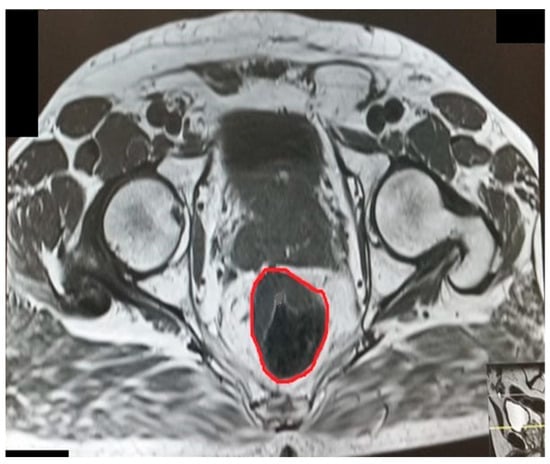

Transverse diameter.

Figure 4.